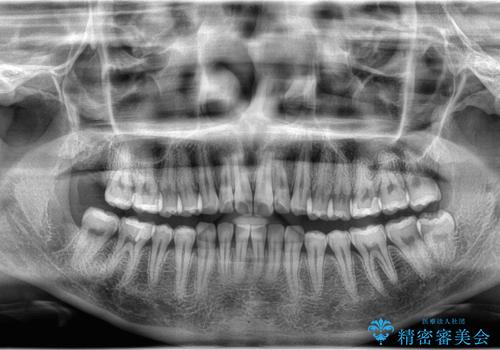

- 下の親知らずは一部分歯肉が被っていたため汚れが溜まりすく、磨き残しにより炎症が生じていました。

抜歯を提案した所希望されたので上下同時に抜歯を行いました。

親知らずは磨きにくく汚れが溜まりやすい場所です。

磨き残しによって親知らずだけでなく、その影響で接してる一つ手前の歯まで虫歯や歯周病のリスクが高くなるため、抜歯をおすすめします。